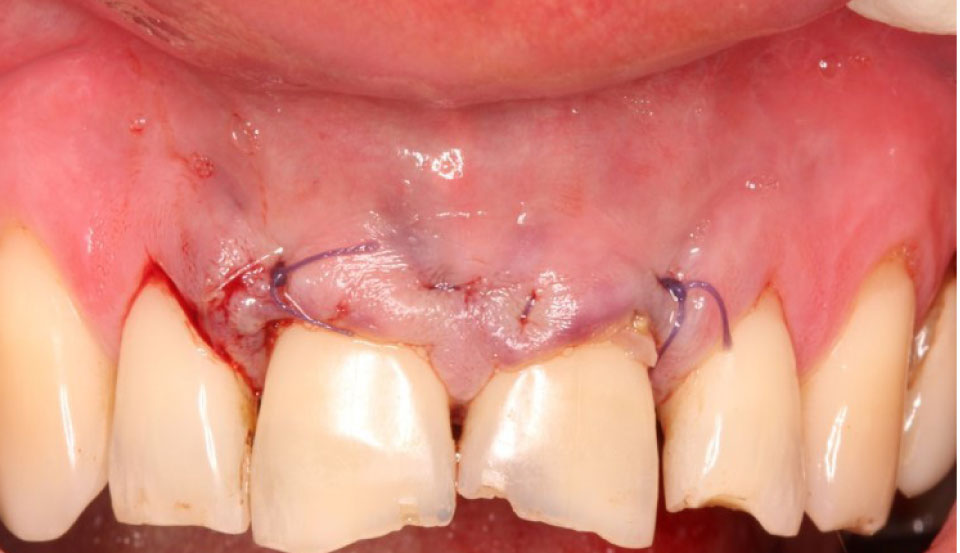

Пациентам молодого возраста 18–44 лет, средний возраст которых равнялся (29,3 ± 4,7) года, проведена оценка состояния микроциркуляторного русла методом лазерной допплеровской флоуметрии. Пациентам, в положении сидя, фиксировали датчик в области десны на расстоянии ниже 2 мм от маргинальной ее части. Оценивали параметр М – показатель микроциркуляции, рассчитываемый в перфузионных единицах, d – среднее квадратичное отклонение, в пф. ед., и Kv – коэффициент вариации, отражающий состояние локального кровотока, в процентах. Оценка ЛДФ-грамм проводилась до начала лечения и через 14 дней после выполненного предпротетического лечения. Гингивэктомию, альвеолопластику и ретракцию десны выполняли по традиционной схеме (рис. 3).

Рис. 3. Пациент Д., 26 лет. Состояние десны после выполненной альвеолопластики